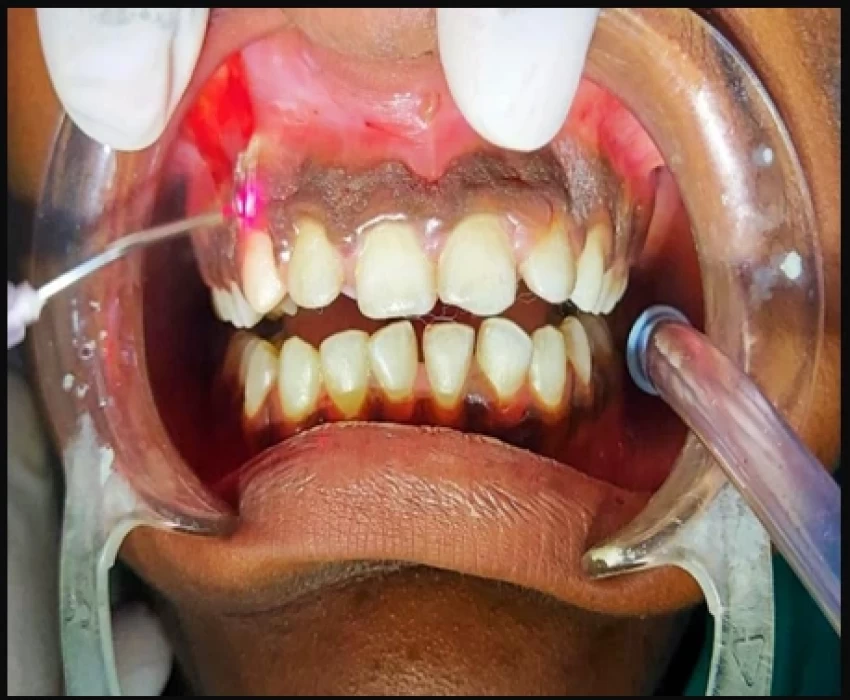

A 15-year-old male patient reported to the Department of Pedodontics, Saraswati dental college, Lucknow, Uttar Pradesh, India with a chief complaint of localized gingival enlargement in the upper anterior teeth region since last 9-10 months.

Idiopathic gingival enlargement with hyperpigmentation

- Gingivectomy, Depigmentation with Laser